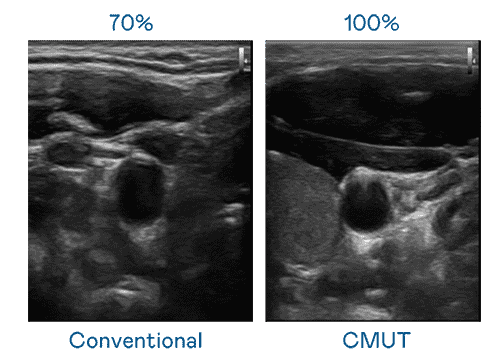

CMUT 技术是一种用电容式微机电元件来产生超音波讯号的技术。。。与传统 PZT 压电式技术相比,,CMUT 频宽增加 30%,,,更宽频的超音波讯号让影像解析度大幅提升,,,,是实现高影像品质医疗超音波扫描、、、、促进精准医疗发展的关键技术。。

大频宽带来超清晰影像

超音波影像的解析度高低,,首先取决于探头能发出的讯号频宽。。森林舞会 CMUT 可提供高清晰的超音波讯号,,,,提供高频宽、、高灵敏度、、影像纹理细节更高的超音波影像,,协助医护人员缩短影像判读时间及利用精准的医疗影像进行诊断。。。